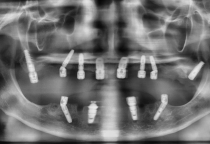

Mỗi phương pháp đều có ưu, nhược điểm riêng. Để đảm bảo an toàn và mang lại nụ cười đẹp, bạn nên đến nha khoa uy tín để được bác sĩ kiểm tra, chụp phim và tư vấn kỹ lưỡng trước khi quyết định.